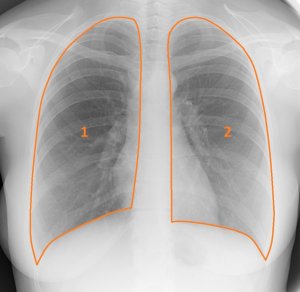

Анализ легочных полей на рентгенограмме

Под легочными полями понимаются те участки снимка, на которые проецировалась легочная ткань. Легочные поля располагаются по обе стороны от тени средостения.

Анализ легочных полей имеет несколько особенностей:

- Правое и левое легочное поле имеют разный размер. Правое, как правило, шире, но короче левого, а левое более узкое и вытянутое. Это считается нормой.

- Срединная тень не должна находиться точно в центре полей. Сердце слегка смещает ее, поэтому у здорового человека тень немного расширена с левой стороны. Это также не указывает на патологию.

- Чтобы было проще анализировать картинку легочных полей, ее делят на 3 части: внутреннюю среднюю и наружную. Каждая зона описывается отдельно.

- Артерии ветвятся в каждом легком по-разному. Поэтому оценивается каждый сегмент легочного поля. В правом легком их 10, в левом – 9.